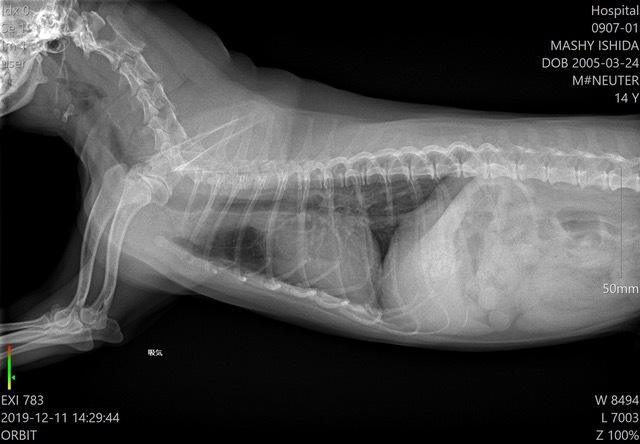

呼吸を吸っているときと、吐いているときで、ずらして撮るとかも簡単にできるのがいいです。

以前はどうしても画像がずれてしまっていたのですが、2枚撮影した画像がピタッと重なって、呼吸器だけが違う画像が撮れます。

それは一番感動しましたね。これは便利だと思いました。

気管虚脱とか気管支拡張症とか呼吸のタイミングで太い細いが分かりやすくて、飼い主さんへの説明もしやすいです。